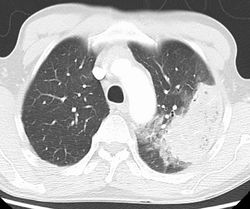

X-ray presentations of pneumonia may be classified as lobar pneumonia, bronchopneumonia, lobular pneumonia, and interstitial pneumonia.[73] Bacterial, community-acquired pneumonia classically show lung consolidation of one lung segmental lobe, which is known as lobar pneumonia.[41] However, findings may vary, and other patterns are common in other types of pneumonia.[41] Aspiration pneumonia may present with bilateral opacities primarily in the bases of the lungs and on the right side.[41] Radiographs of viral pneumonia may appear normal, appear hyper-inflated, have bilateral patchy areas, or present similar to bacterial pneumonia with lobar consolidation.[41] Radiologic findings may not be present in the early stages of the disease, especially in the presence of dehydration, or may be difficult to interpret in the obese or those with a history of lung disease.[24] Complications such as pleural effusion may also be found on chest radiographs. Laterolateral chest radiographs can increase the diagnostic accuracy of lung consolidation and pleural effusion.[40]

A CT scan can give additional information in indeterminate cases[41] and provide more details in those with an unclear chest radiograph (for example occult pneumonia in chronic obstructive pulmonary disease). They can be used to exclude pulmonary embolism and fungal pneumonia, and detect lung abscesses in those who are not responding to treatments.[40] However, CT scans are more expensive, have a higher dose of radiation, and cannot be done at bedside.[40]